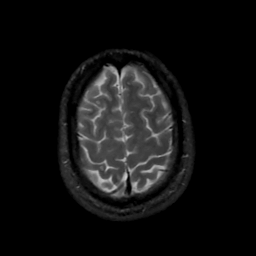

MR Study #15, June 9, 1991 -- Slice #42